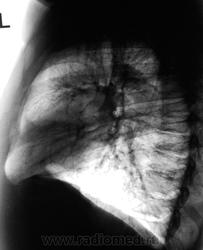

Уменьшение пневматизации нижней доли, плевро-медиастино-диафрагмальные спайки, деформация диафрагмы, средостения-больше данных за посттравматические изменения органов грудной клетки, + диафрагмальная грыжа.

Понял, а не допускаете мысли, что могла быть операция на лёгком с резекцией ребра ( хорошо виден фрагмент заднего отрезка V ребра слева, с абсолютно нормальной костной структурой, что нехарактерно для метастатического поражения ребра ).

Наверное не спайки, а уже шварты.

Нарушение проходимости "среднедолевого или их?" бронха слева, гиповентиляция язычковых сегментов, тень в верхнем средостении. Центральный рак.

Коллеги, не вижу V ребра слева ( это мне подсказал, коллега который просматривает сайт). Как это расценивать?